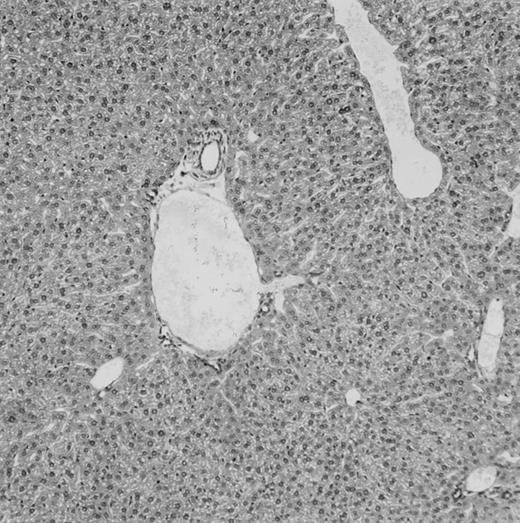

Histologic findings. Organs were collected at different times after BMT and tissue sections were stained with hematoxylin and eosin. Original magnifications for spleen (left) and liver (right) are ×40 and ×100, respectively. (A) B6 mice receiving FVB BM plus EpTK T cells. (B) Control group receiving BM only.

FVB BM-grafted B6 mice: a model of lethal GVHD.We developed a model of GVHD resulting in 100% mortality soon after BMT using FVB mice, a strain not previously used as BM donors in experimental allogeneic BMT. We tested different combinations of recipient irradiation doses, as well as injected BM cell and CD3+ peripheral T-cell numbers. When 10-Gy–irradiated B6 mice were reconstituted with 107 FVB BM cells, we observed prolonged survival, whereas all ungrafted animals died before day 16 (Fig 2). In these conditions, more than 98% of splenocytes were of donor origin (Fig 3A). When 107 CD3+ peripheral T cells from mice of FVB genetic background were added to the FVB BMT, all animals died of GVHD between days 7 and 34 (Fig 2). Similar results were obtained using either PBS-treated mice receiving EpTK or EpΔTK peripheral T cells or GCV-treated mice receiving FVB nontransgenic peripheral T cells. Notably, this observation also indicates that both TK- and ΔTK-expressing T cells in the absence of GCV are fully competent to induce a lethal GVHD. Histopathologic examination of spleen and liver of these animals showed characteristic GVHD lesions such as (1) architecture disruption, necrosis, and congestion in the spleen; (2) hepatic periportal necrosis; (3) mononuclear portal infiltrates; and (4) endothelialitis of portal or centrolobular veinules (Fig 4A). By comparison, B6 mice receiving only FVB BM had a normal histology (Fig 4B).

Using this delivery mode, we observed that mice receiving a 7-day GCV treatment initiated at the time of transplantation were protected from GVHD. At day 60, the survival rate was 100% in the GCV-treated group receiving EpTK CD3+ T cells, and was still 92% at the end of a 120 day follow-up (Fig 2A). Protected mice were apparently healthy, presented no visible skin lesions, and gained weight comparably to controls receiving only BM (data not shown). Hematologic reconstitution was analyzed by flow cytometry at different times from day 14 to day 212. Splenocytes of GCV-treated animals were of donor H-2q origin in the B-cell (B220+) and non–B-cell (B220−) compartments, the latter containing donor Thy1.1+ T cells but no recipient Thy1.2+ T cells (Fig 3B). Finally, histological analysis in these animals showed nodular architecture in the spleen and no significant hepatocyte necrosis or portal mononuclear cell infiltrates in the liver (not shown) and similar to control animals receiving only BM. Taken together, these data indicate that a GCV treatment, administered at the onset of allogeneic BMT and with a course as short as 7 days, abrogates GVHD and allows a full recovery from the lethal irradiation.